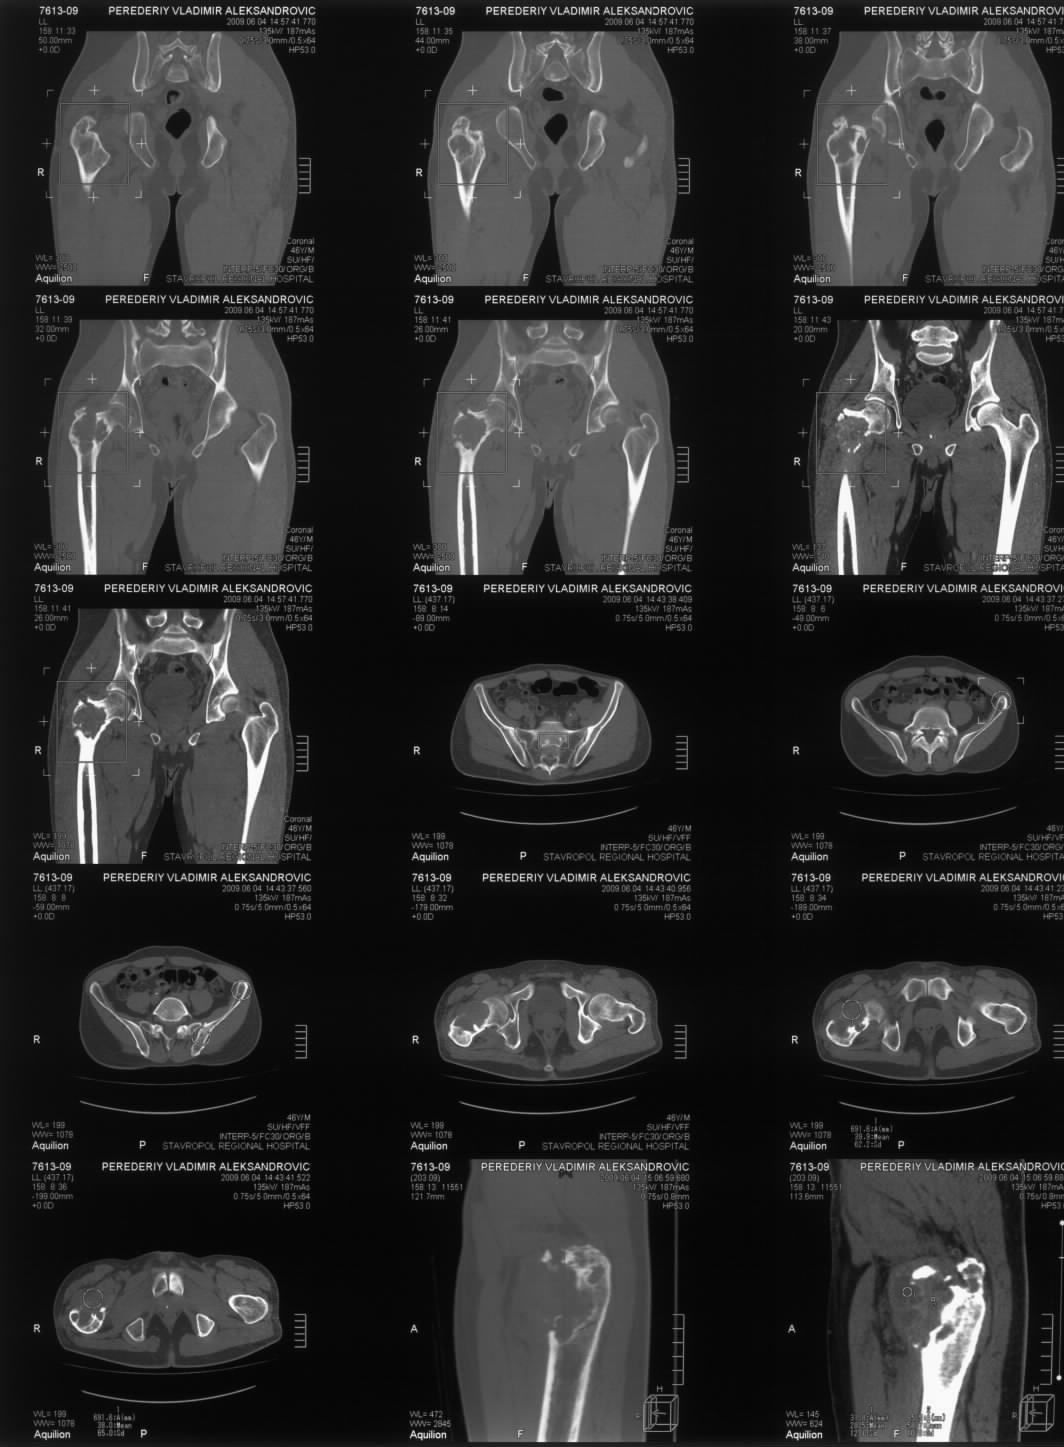

Диагноз: Ангиосаркома проксимального отдела правой бедренной кости. Патологический перелом шейки бедренной кости. Множественные метастазы в легкие, позвоночник, ребра, кости таза.

Считает себя больным с 2005 года, когда впервые появились боли в правом тазобедренном суставе с иррадиацией в поясничную область. Лечился по месту жительства по поводу поясничного остеохондроза, люмбоишиалгии. Отмечает постепенное усиление болей в области правого тазобедренного сустава. С августа 2007 года появилась хромота. В 2008 году была выполнена рентгенография тазобедренного сустава, выявлен патологический очаг в проксимальном отделе бедренной кости. Консультирован онкологом. Обследовался стационарно в травматолого-ортопедическом отделении №1 ГУЗ «СККЦ СВМП». Была выполнена операционная биопсия. Заключение: «наиболее вероятна картина гемангиоэндотелиомы с явлениями пролиферации и атипии». Для дальнейшего лечения был направлен в РОНЦ им. Н.Н.Блохина РАМН. Повторно была выполнена операционная биопсия с иммуногистохимическим исследованием материала. Заключение: «морфологическая картина более всего соответствует ангиосаркоме». Получил курс лучевой терапии. Планировалась повторная госпитализация для органосохраняющего оперативного лечения. Однако до настоящего времени госпитализация не состоялась.

31.05.09 упал дома с высоты собственного роста. Появились сильные боли в правом тазобедренном суставе. Самостоятельно обратился в ГУЗ «СККЦ СВМП». При клиническом обследовании и рентгенографии был диагностирован патологический перелом шейки бедренной кости. Объективно: